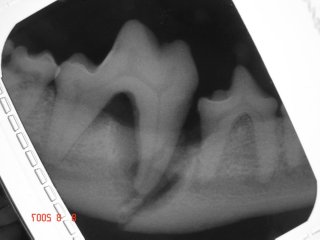

Dental x-ray reveals the significant bone loss around the mesial root and fractured jaw bone. Severe bone loss around the mesial root of this lower first molar tooth is caused by periodontal disease which eventually led to jaw fracture between the fourth premolar tooth and first molar tooth.